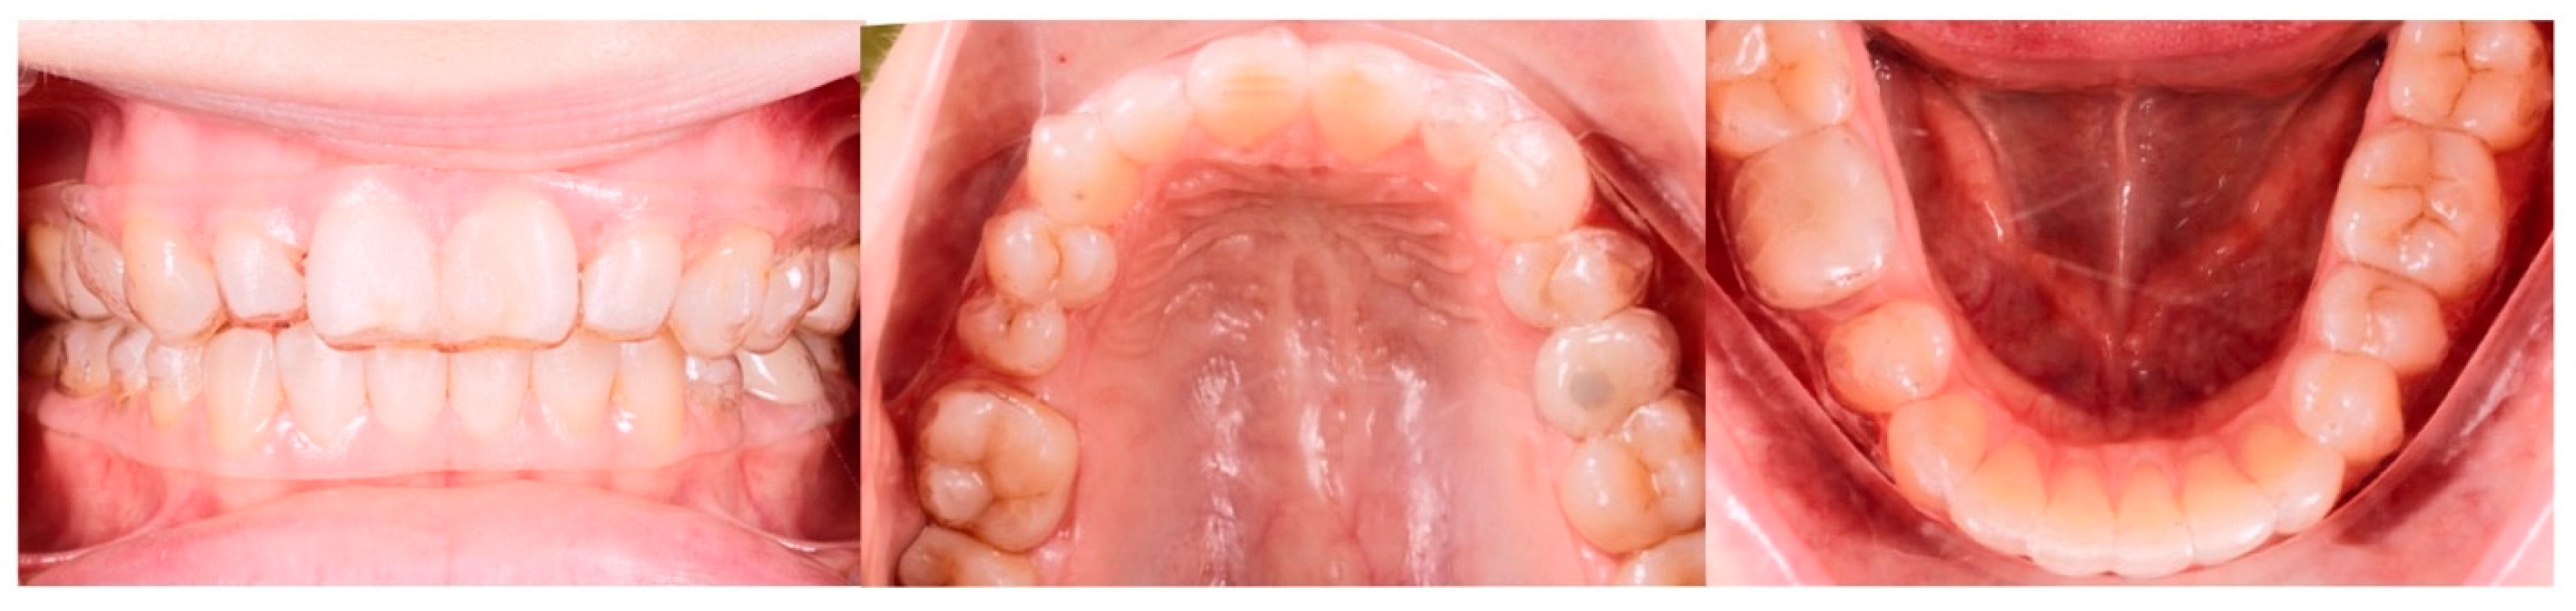

2.1. Pre-Treatment Records and Analysis

2.2. Pre-Treatment Diagnosis